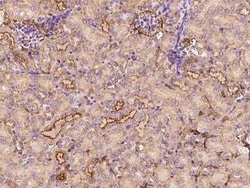

CLEC3B/Tetranectin Polyclonal antibody specifically detects CLEC3B/Tetranectin in Mouse samples. It is validated for Western Blot, ELISA, Immunohistochemistry (Paraffin)Especificaciones

| Western Blot 1:500-1:2000, ELISA 1:5000-1:10000, Immunohistochemistry-Paraffin 1:500-1:2000 | |